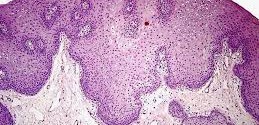

La hipoplasia dérmica focal es una enfermedad rara del grupo de las displasias (desarrollo anómalo de tejidos u órganos) ectodérmicas. La hipoplasia dérmica focal es un trastorno cutáneo polimórfico con anomalías muy variables que afectan a los ojos, dentadura, esqueleto, y a los sistemas nervioso central, urinario, gastrointestinal y cardiovascular. Esta displasia se considera una genodermatosis (grupo de dermatosis hereditarias …